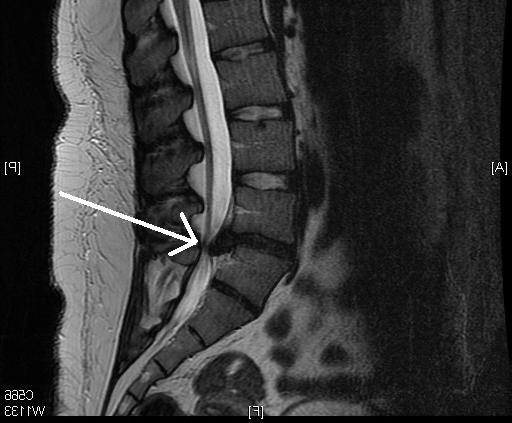

Врачи отмечают, что диагностика неврита седалищного нерва требует комплексного подхода. Основными методами являются клинический осмотр, магнитно-резонансная томография и электромиография. Эти исследования помогают определить степень повреждения нерва и выявить возможные причины, такие как травмы или воспалительные процессы.

Чтобы установить причину недомогания, специалист назначает диагностическое исследование. Пациенту нужно лечь на спину и поднять одну ногу вверх. Если это вызывает резкую боль, вероятно, имеются проблемы с седалищным нервом. Для подтверждения диагноза потребуется:

- компьютерная или магнитно-резонансная томография, либо другой метод медицинской визуализации.

Диагностические процедуры помогают выявить патологии и заболевания, которые могут развиваться на их основе.

К сожалению, распознать патологические процессы, затрагивающие седалищный нерв, полагаясь только на жалобы пациента, невозможно. Поэтому при наличии жалоб назначается инструментальная диагностика, и в большинстве случаев это — магнитно-резонансная томография.

Для точного определения места защемления седалищного нерва проводится нейроортопедический осмотр. Методы визуализации такие как МРТ и, по надобности, нейромиография. Пораженные межпозвонковые диски оказывают компрессию на нервные корешки в поясничном отделе позвоночника.